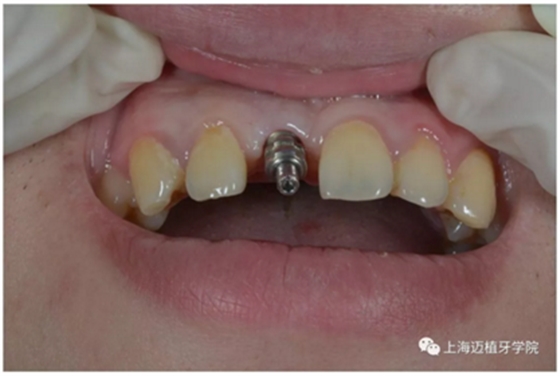

3月后恢復(fù)良好,上愈合基臺

2周后袖口成形

戴牙前口內(nèi)照片:

去除愈合基臺: